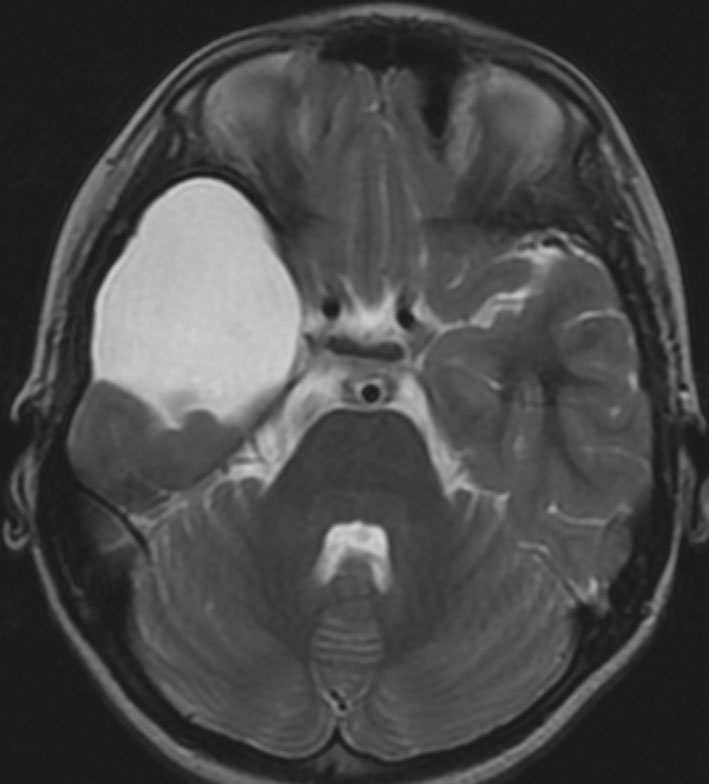

シルビウス裂くも膜のう胞,中頭蓋窩くも膜のう胞

最も多いタイプで50%くらいです。7歳の子に偶然発見された右シルビウス裂のくも膜のう胞です。大きいのですがこの程度では治療の必要はありません。シルビウス裂のくも膜のう胞は最も多いものです。